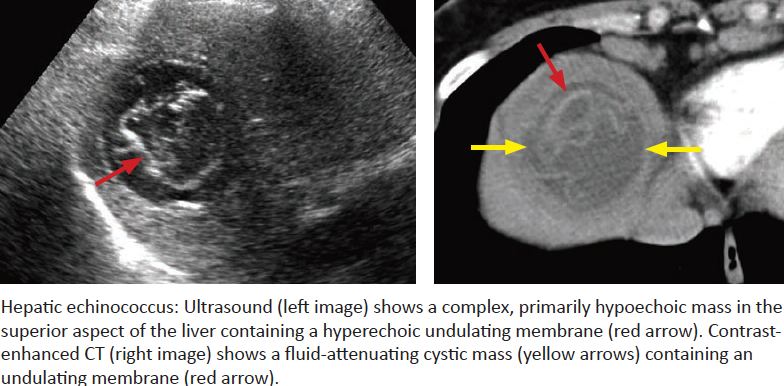

Echinococcal Disease

Caused by what?

Endemic Where?

Associated with what specific job?

Imaging Characteristics?